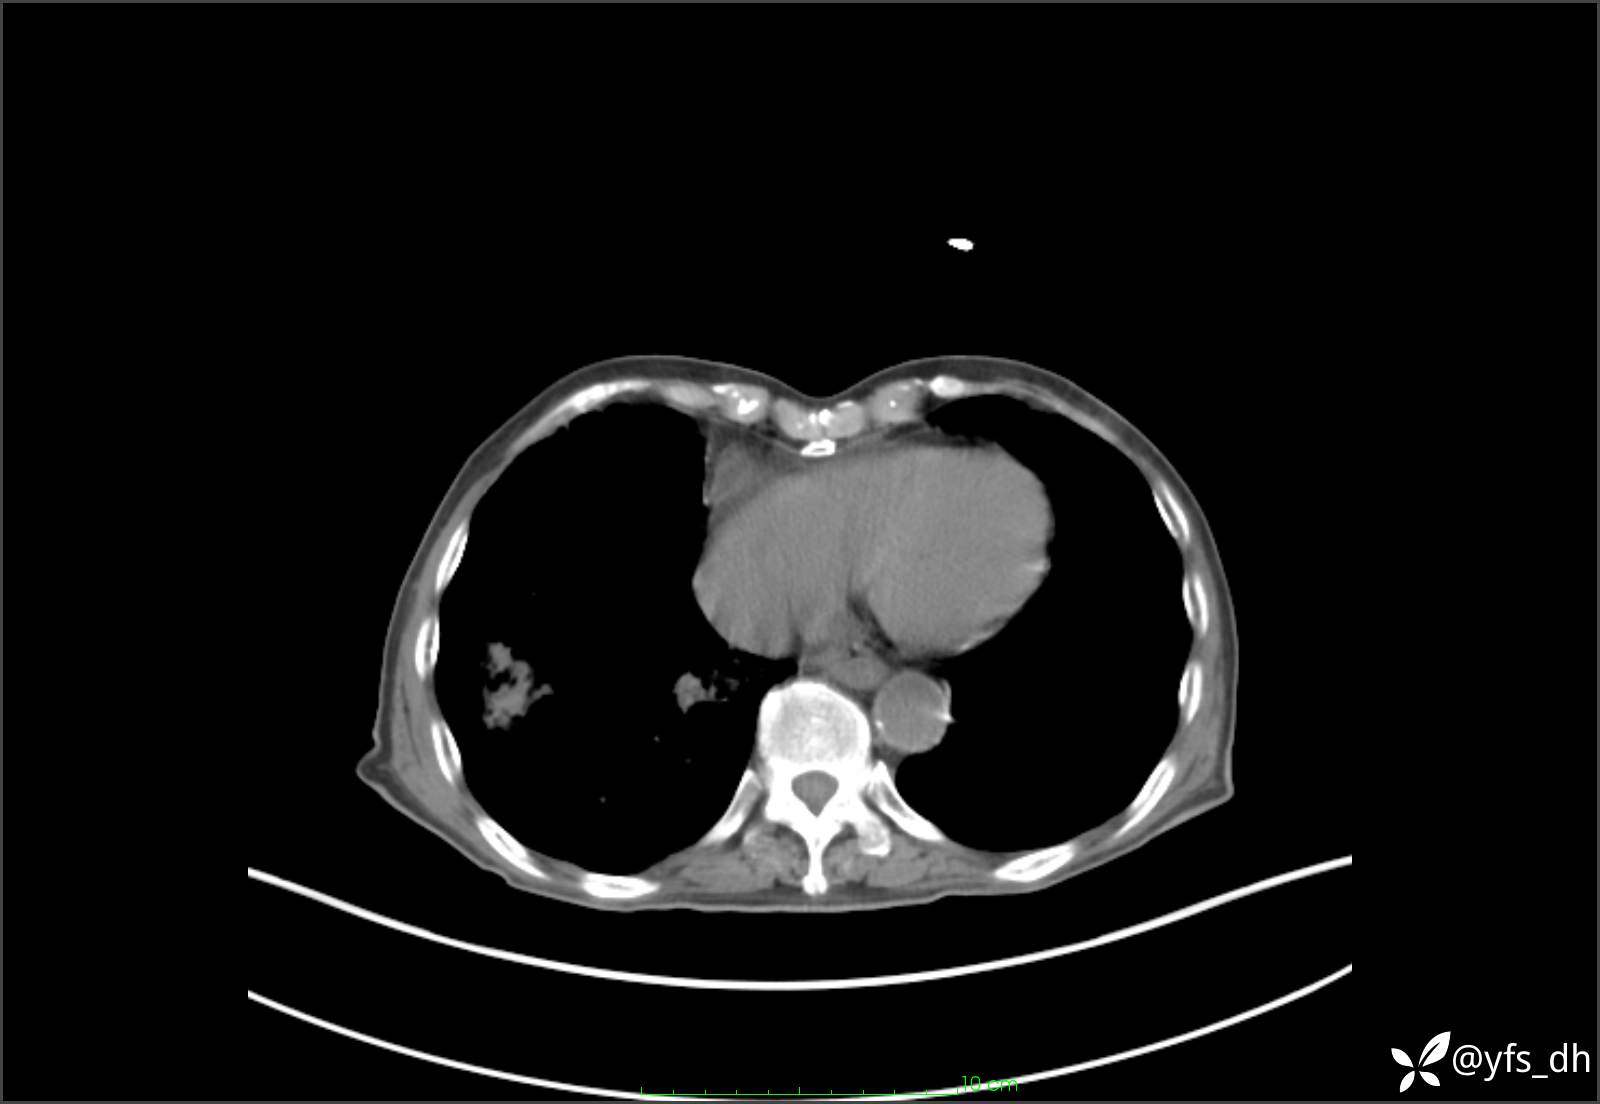

1.简要病史:患者4天前突发上腹部疼痛不适,但可以忍受。3小时前饭后突然加重,不能忍受后就诊。

2.简要手术记录:术中见腹盆腔大量肠液及粪便,乙状结肠中下段见一约3cm的破口。